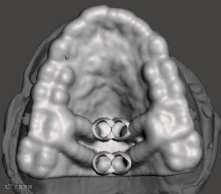

CBCT精准定位

种植导板设计及打印

我们能为您提供MSE的数字化精准定位

提供个性化的MSE支抗钉植入导板

以确保MSE的精准制作